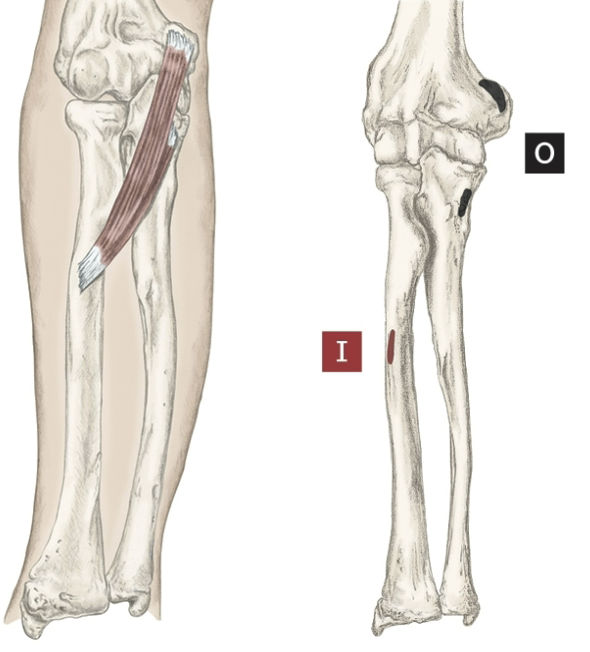

Action of Flexor Digitorum Profundus

Flexion of 2-5 fingers [ MCP,PIP,DIP]

Origin of Flexor Digitorum Profundus

Proximal ulna and anterior, and medial

Insertion of Flexor Digitorum Profundus

Base of palmar surface of distal phalanges 2-5

Nerve that the Flexor Digitorum Profundus innervates

Median Nerve